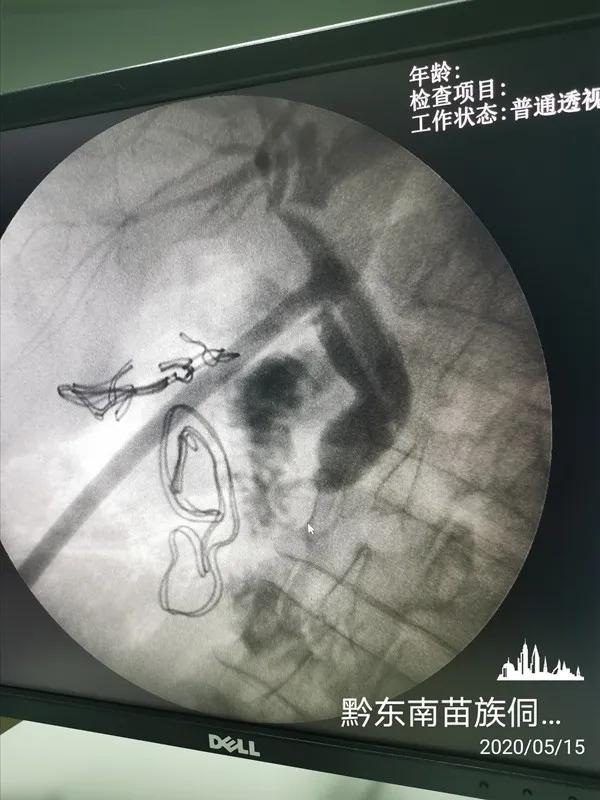

普外科主任医师蒋天业对普外科医生开展腹腔镜胆囊等手术的开展教学。并对肝内胆管患者进行术中胆系造影技术为普外科开展了新技术,为从江县人民带来了更好的医疗救治。